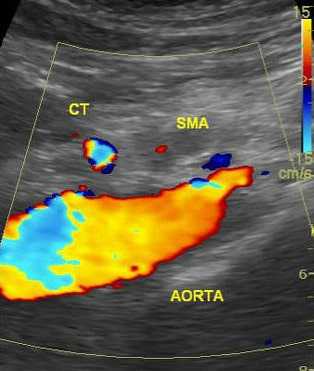

![УЗИ картина закупорки верхней брыжеечной артерии]()

УЗИ брюшной аорты

Своевременная диагностика является залогом успеха в лечении абдоминальной ишемии, но она очень сложна. Учитывая, что возможность спасти жизнь при этой патологии имеется только в первые часы заболевания диагностика должна быть срочной и точной. Мезентриальный тромбоз можно спутать с любым острым заболеванием брюшной полости. Диагноз ставится методом исключения. В первую очередь необходимо исключить прободную язву, острый панкреатит, кишечную непроходимость. Наличие у пациента мерцательной аритмии, инфарктов в анамнезе, атеросклероза нижних конечностей позволяют предположить мезентериальный тромбоз. После исключения острых заболеваний брюшной полости проводятся специфические исследования для диагностики непроходимости сосудов брыжейки.

УЗИ брюшной аорты позволяет выявить тромбоз брыжеечной артерии или чревного ствола. Преимуществом метода является его быстрая доступность и отсутствие осложнений. Брюшная аорта осматривается в продольном и в поперечном срезе в режиме цветового картирования. Определяется скорость кровотока по аорте и ее ветвям. Метод обладает достаточно высокой чувствительностью, но его результаты зависят от опыта врача, проводящего исследование и правильной интерпретации полученных данных.